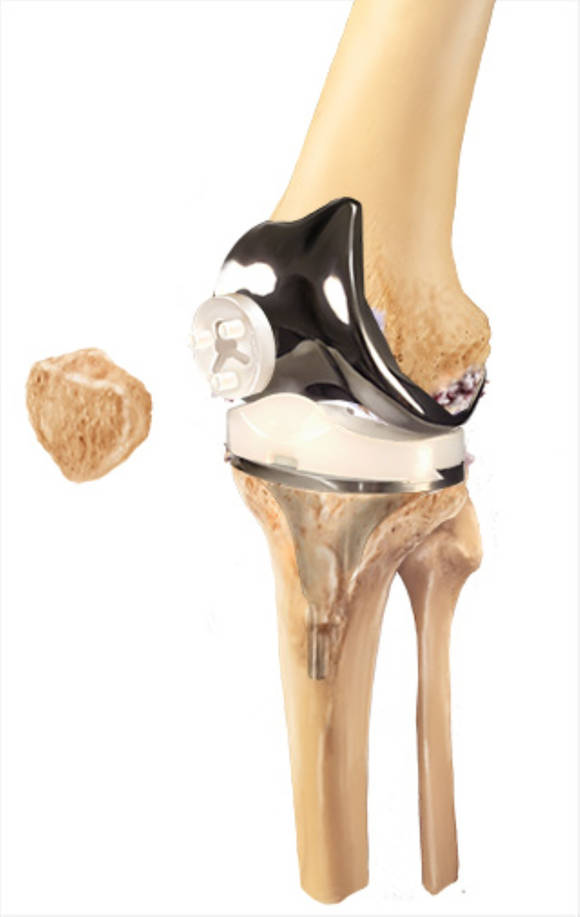

카티스템은 국내 메디포스트에서 개발한 제대혈 유래 줄기세포 치료제입니다.

타인의 제대혈에서 얻은 줄기세포를 배양·정제해 만들어진 ‘동종 줄기세포’ 제품이죠.

이미 2012년 식품의약품안전처(MFDS) 허가를 받은,

세계 최초의 제대혈 줄기세포 기반 연골 재생 치료제 중 하나입니다.

이 치료는 단순히 주사로 넣는 게 아니라,

수술 중 연골이 손상된 부위에 줄기세포를 직접 이식하는 방식입니다.

이 때문에 시술 난도가 높고, 수술비용이 자가지방 줄기세포보다 훨씬 비쌉니다.

하지만 임상 연구에 따르면 카티스템 이식 부위에서 히알린(hyaline) 형태의 새로운 연골조직이 자라나고,

10년 이상 장기 추적 결과에서도 효과가 지속된 사례가 보고되고 있습니다.